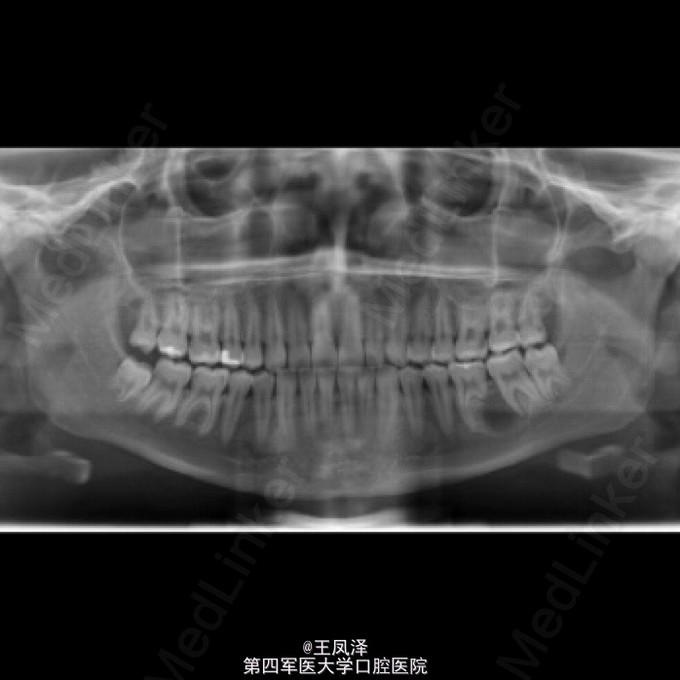

罕见左侧下颌骨牙本质生成性影细胞瘤一例

患者,女,20岁,自诉左侧下颌磨牙区疼痛不适,不能咀嚼来诊

以巨大囊肿为表现的牙本质生成性影细胞瘤